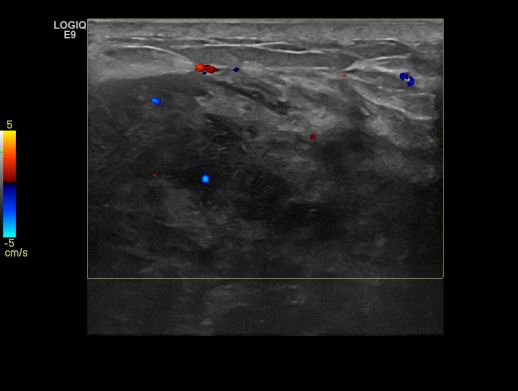

상기환자 검진상 이상 소견으로 내원하신 60대 여성분으로  본원 초음파 시행 후

우측 유두 밑 조직검사 시행하여 우측 악성 진단 받았습니다.